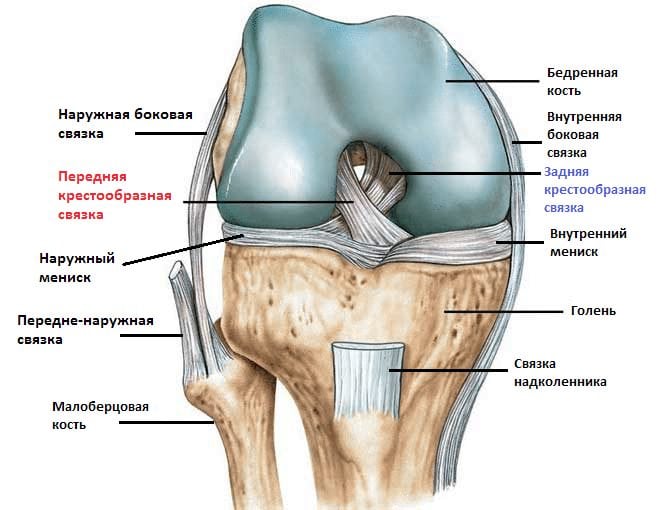

Коленный сустав сохраняет стабильность при движении благодаря мощному связочно-сухожильному аппарату. Он состоит из передней и задней крестообразных связок, большеберцовой коллатеральной (внутренней боковой) и малоберцовой коллатеральной (наружной боковой) связок. Основная функция крестообразных структур — удержание голени от смещения кпереди и кзади, коллатеральных — предупреждение отклонения сустава кнаружи и кнутри.

Задняя крестообразная связка (ЗКС) считается одним из самых прочных элементов колена, поэтому ее разрывы редко бывают изолированными. В момент травмы нередко одновременно повреждаются такие связки:

- передняя крестообразная;

- наружная и (или) внутренняя боковые.